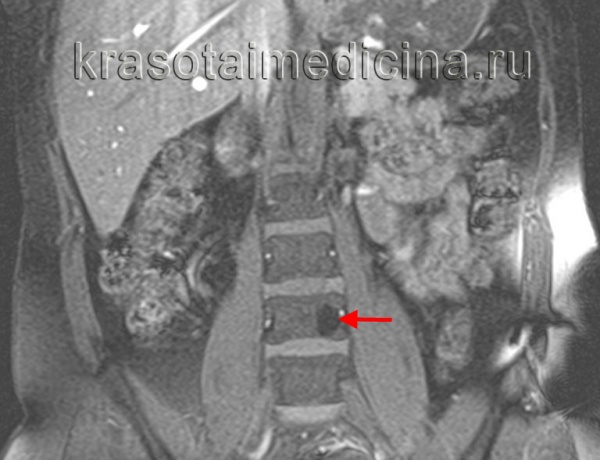

(Слева) На аксиальной КТ без КУ визуализируется относительно хорошо отграниченный участок без склеротического ободка. Ключевые диагностические признаки: «жировая» плотность и картина «пчелиных сот».

(Справа) На сагиттальной реформатированной КТ определяется гиподенсный участок в теле СЗ с немногочисленными утолщенными трабекулами, ориентированными вертикально (характерные КТ-признаки гемангиомы позвонка). Вертикальные трабекулы не всегда соединяют обе замы кегельные пластинки.